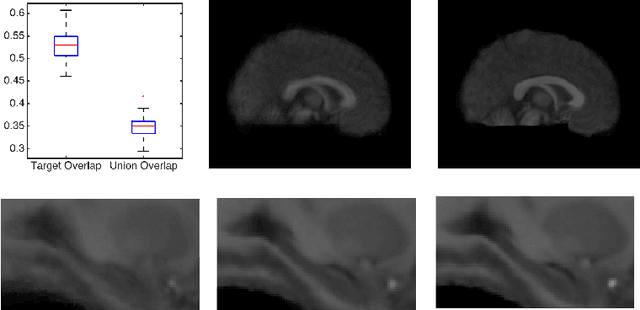

Abstract:Segmenting vascular pathologies such as white matter lesions in Brain magnetic resonance images (MRIs) require acquisition of multiple sequences such as T1-weighted (T1-w) --on which lesions appear hypointense-- and fluid attenuated inversion recovery (FLAIR) sequence --where lesions appear hyperintense--. However, most of the existing retrospective datasets do not consist of FLAIR sequences. Existing missing modality imputation methods separate the process of imputation, and the process of segmentation. In this paper, we propose a method to link both modality imputation and segmentation using convolutional neural networks. We show that by jointly optimizing the imputation network and the segmentation network, the method not only produces more realistic synthetic FLAIR images from T1-w images, but also improves the segmentation of WMH from T1-w images only.